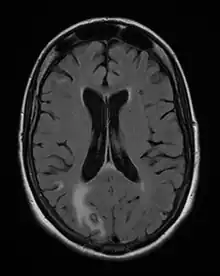

Acute toxoplasmosis is often asymptomatic in healthy adults.[13][14] However, symptoms may manifest and are often influenza-like: swollen lymph nodes, headaches, fever, and fatigue,[15] or muscle aches and pains that last for a month or more. It is rare for a human with a fully functioning immune system to develop severe symptoms following infection. People with weakened immune systems are likely to experience headache, confusion, poor coordination, seizures, lung problems that may resemble tuberculosis or Pneumocystis jiroveci pneumonia (a common opportunistic infection that occurs in people with AIDS), or chorioretinitis caused by severe inflammation of the retina (ocular toxoplasmosis).[15] Young children and immunocompromised people, such as those with HIV/AIDS, those taking certain types of chemotherapy, or those who have recently received an organ transplant, may develop severe toxoplasmosis. This can cause damage to the brain (encephalitis) or the eyes (necrotizing retinochoroiditis).[16] Infants infected via placental transmission may be born with either of these problems, or with nasal malformations, although these complications are rare in newborns. The toxoplasmic trophozoites causing acute toxoplasmosis are referred to as tachyzoites, and are typically found in various tissues and body fluids, but rarely in blood or cerebrospinal fluid.[17]

Diagnosis of toxoplasmosis in humans is made by biological, serological, histological, or molecular methods, or by some combination of the above.[61] Toxoplasmosis can be difficult to distinguish from primary central nervous system lymphoma. It mimics several other infectious diseases so clinical signs are non-specific and are not sufficiently characteristic for a definite diagnosis. As a result, the possibility of an alternative diagnosis is supported by a failed trial of antimicrobial therapy (pyrimethamine, sulfadiazine, and folinic acid (USAN: leucovorin)), i.e., if the drugs produce no effect clinically and no improvement on repeat imaging.